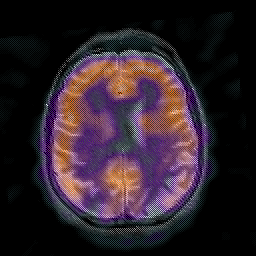

Alzheimer's disease: overlay -- Slice #34

[Home][Help][Clinical] Slice 34